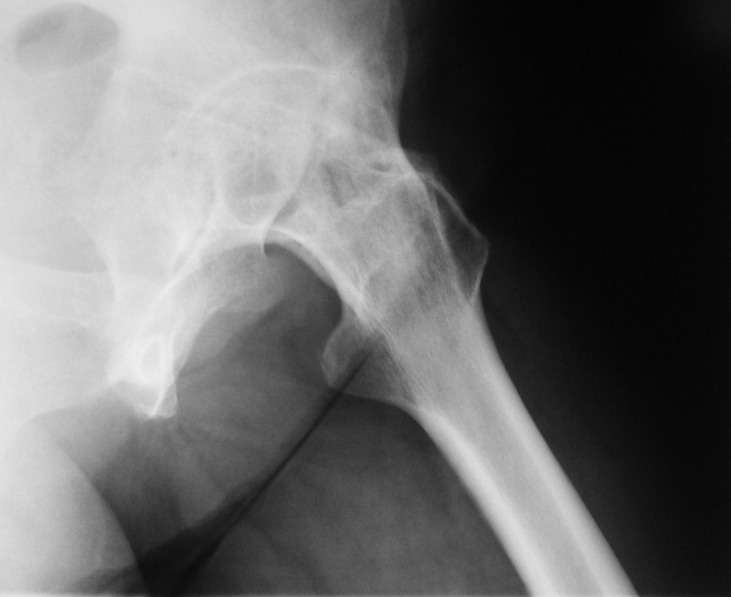

У больной 53 лет в последний год появились сильные боли в пояснице.

При обследовании выявлен анкилоз тазобедренного сустава в приведении. Видимо, в период пребывания в тяжелом состоянии появились гетеротопические оссификаты. За исключением того, что осталась одна почка, сейчас других медицинских проблем нет.

Пациентку в первую очередь беспокоят боли в спине, на отсутствие движений в суставе она вроде и не жалуется. Вопрос насчет тактики. Корсет и анальгетики вряд ли решение. Первый вариант - удаление оссификатов и эндпротезирование, второй - корригирующая остеотомия в проксимальном отделе с устранением порочного положения.

Второй вариант много проще и менее травматичен. Можно ли без размыкания сустава рассчитывать на существенное уменьшение боли за счет устранения перекоса таза?